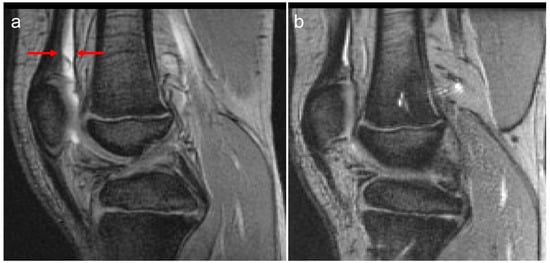

Figure 1.

Ten-year-old boy (at baseline MRI) with severe hemophilia A, without prior left knee bleed history and no inhibitory antibodies. Baseline (a) and follow-up (b) MRI (a) examinations of the left knee show reversible soft tissue changes (effusion/hemarthrosis) of the knee. (a) The baseline sagittal multiplanar gradient-recalled (MRGR) MR image demonstrates an International Prophylaxis Study Group (IPSG) MRI score of 1: soft tissue domain = 1 (effusion/hemarthrosis = 1, arrows); osteochondral domain = 0. (b) The follow-up MR images fail to show any evidence of soft tissue or osteochondral tissue changes. Follow-up IPSG MRI score = 0; soft tissue domain = 0; osteochondral domain = 0. A physiological amount of fluid is seen within the left knee joint.